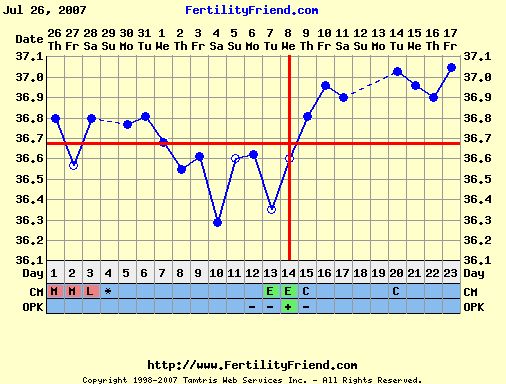

Ha valaki nem tudná "kiolvasni", mit lát, segítek: az első képen a drágánk feje jobb ldalt (a másikon is

) , aztán a kis teste, a cicije felett a pici folt az egyik keze, aztán egy nagy pocak, majd valahogy a lábai (egy pár lábujjacskája látható!

)

A másik képenközelebbről van a buksija, lehet látni a nóziját, meg az éppen csókra álló száját!!

Ja, és amikor uh-zott a doki, kitátotta a száját, vissza is játszotta BB, mondta, hogy tök érdekes, még ilyen pici, és nyitogatja a száját! Hát egész nap vigyorogtunk, úgy örültünk! Tényleg nagyon jó volt látni!

Ő a kisfiúnk, csak így tudtuk lefotózni, ennél jobban nem mutatta a kis pofiját.

Ő a kisfiúnk, csak így tudtuk lefotózni, ennél jobban nem mutatta a kis pofiját.